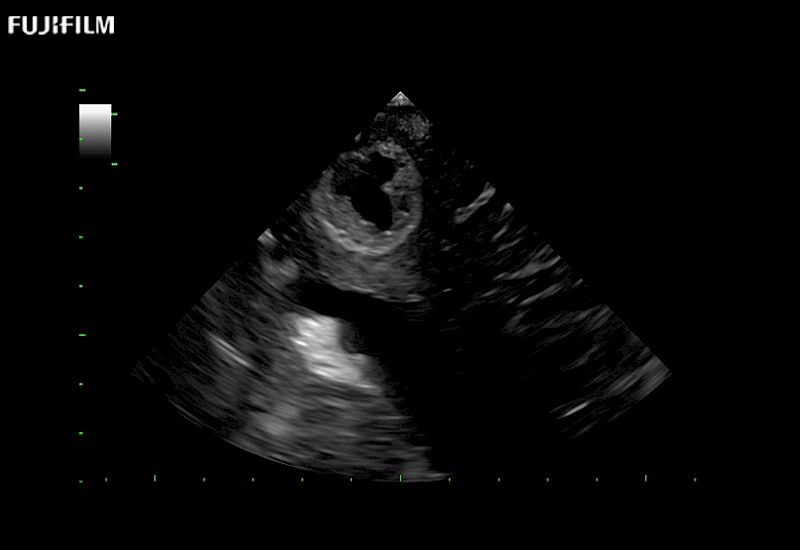

The world's only phased array burr-hole transducer that is ideal for scanning during burr-hole guidance procedures.

Main Specifications: